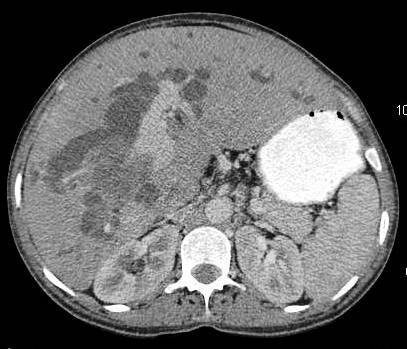

Figure 2: diffuse infiltrative carcinoma of the gallbladder with irregular wall thickening and invasion of liver parenchyma. Medially the plane with second part of duodenum is invaded. Inferiorly right perinephric fat plane invaded